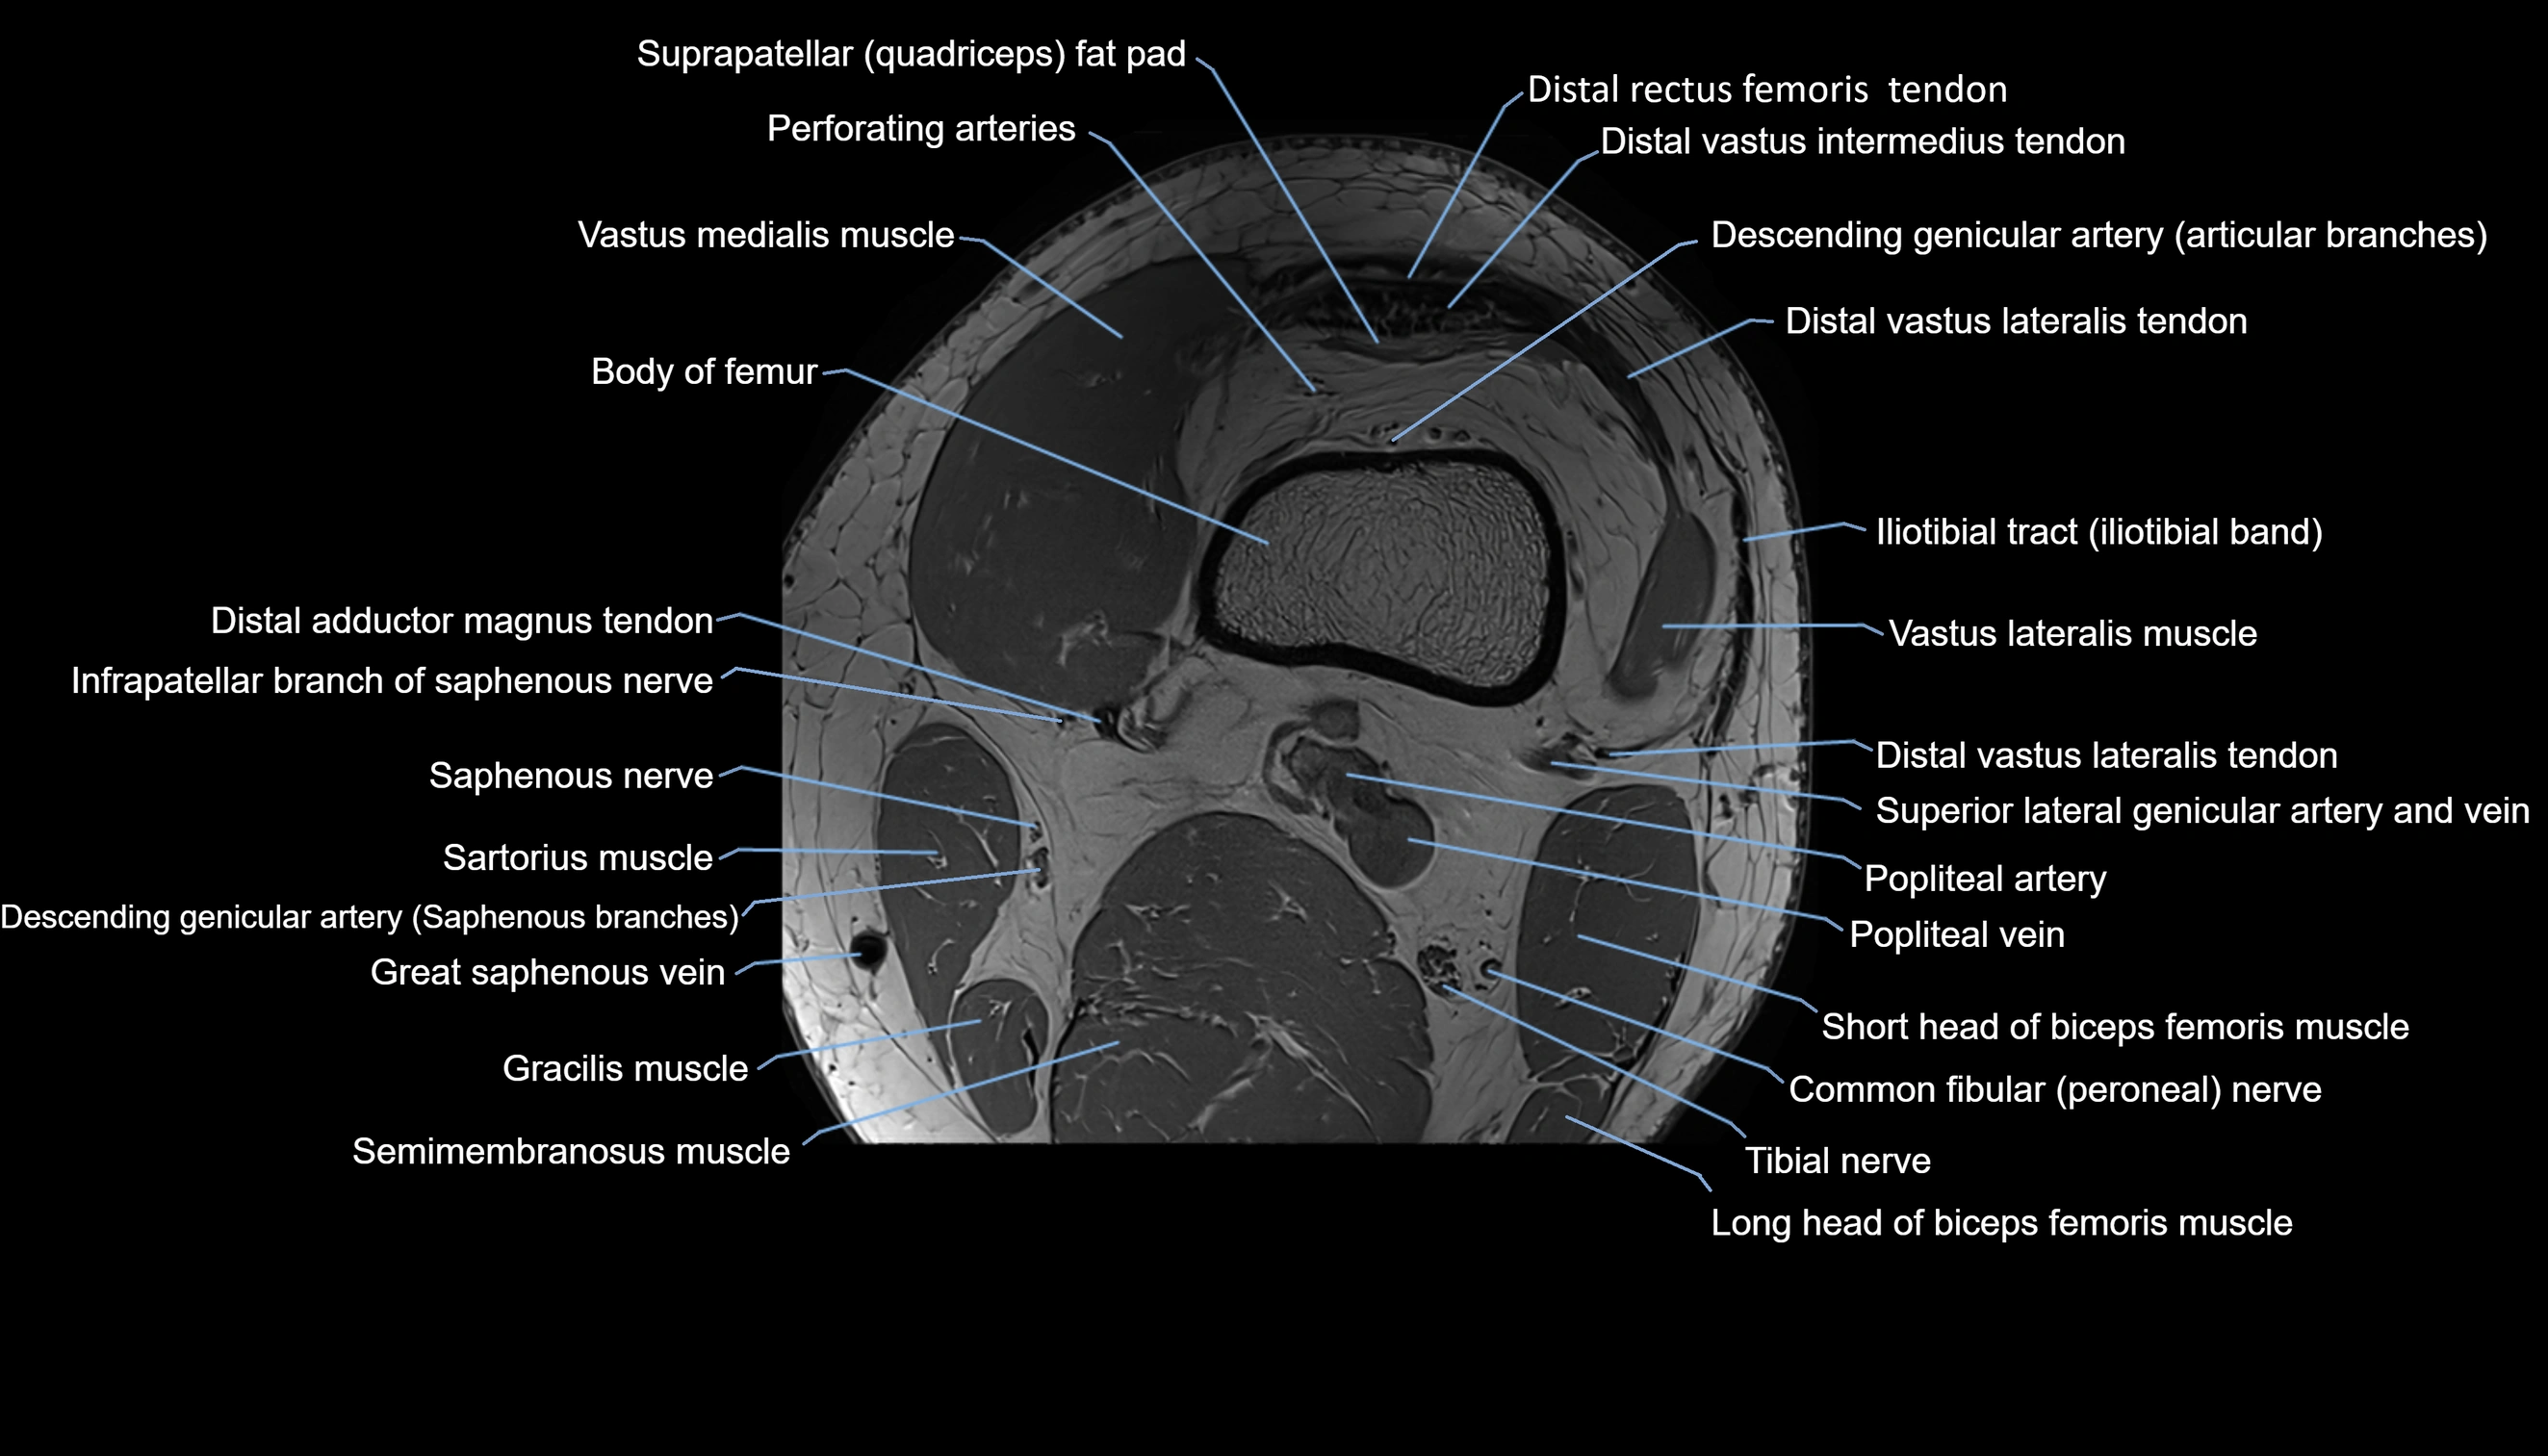

- Body of femur

- Perforating Arteries (Knee joint)

- Popliteal artery

- Popliteal vein

- Saphenous nerve

- Sartorius muscle

- Semimembranosus muscle

- Tibial nerve

- Vastus lateralis muscle

- Vastus medialis muscle

- great saphenous vein